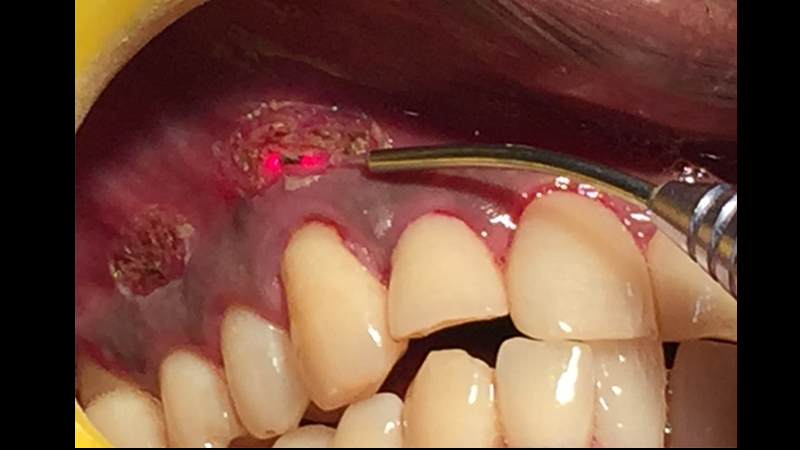

در هنگام تصمیمگیری برای دریافت خدمات درمانی، بهویژه در حوزه دندانپزشکی، یکی از اولین سؤالاتی که به ذهن متبادر میشود، هزینه آن است. با ظهور فناوریهای نوین مانند لیزر، بسیاری از بیماران با این پرسش مواجه میشوند که آیا هزینههای بالاتر درمانهای لیزری در مقایسه با روشهای سنتی، توجیهپذیر است؟